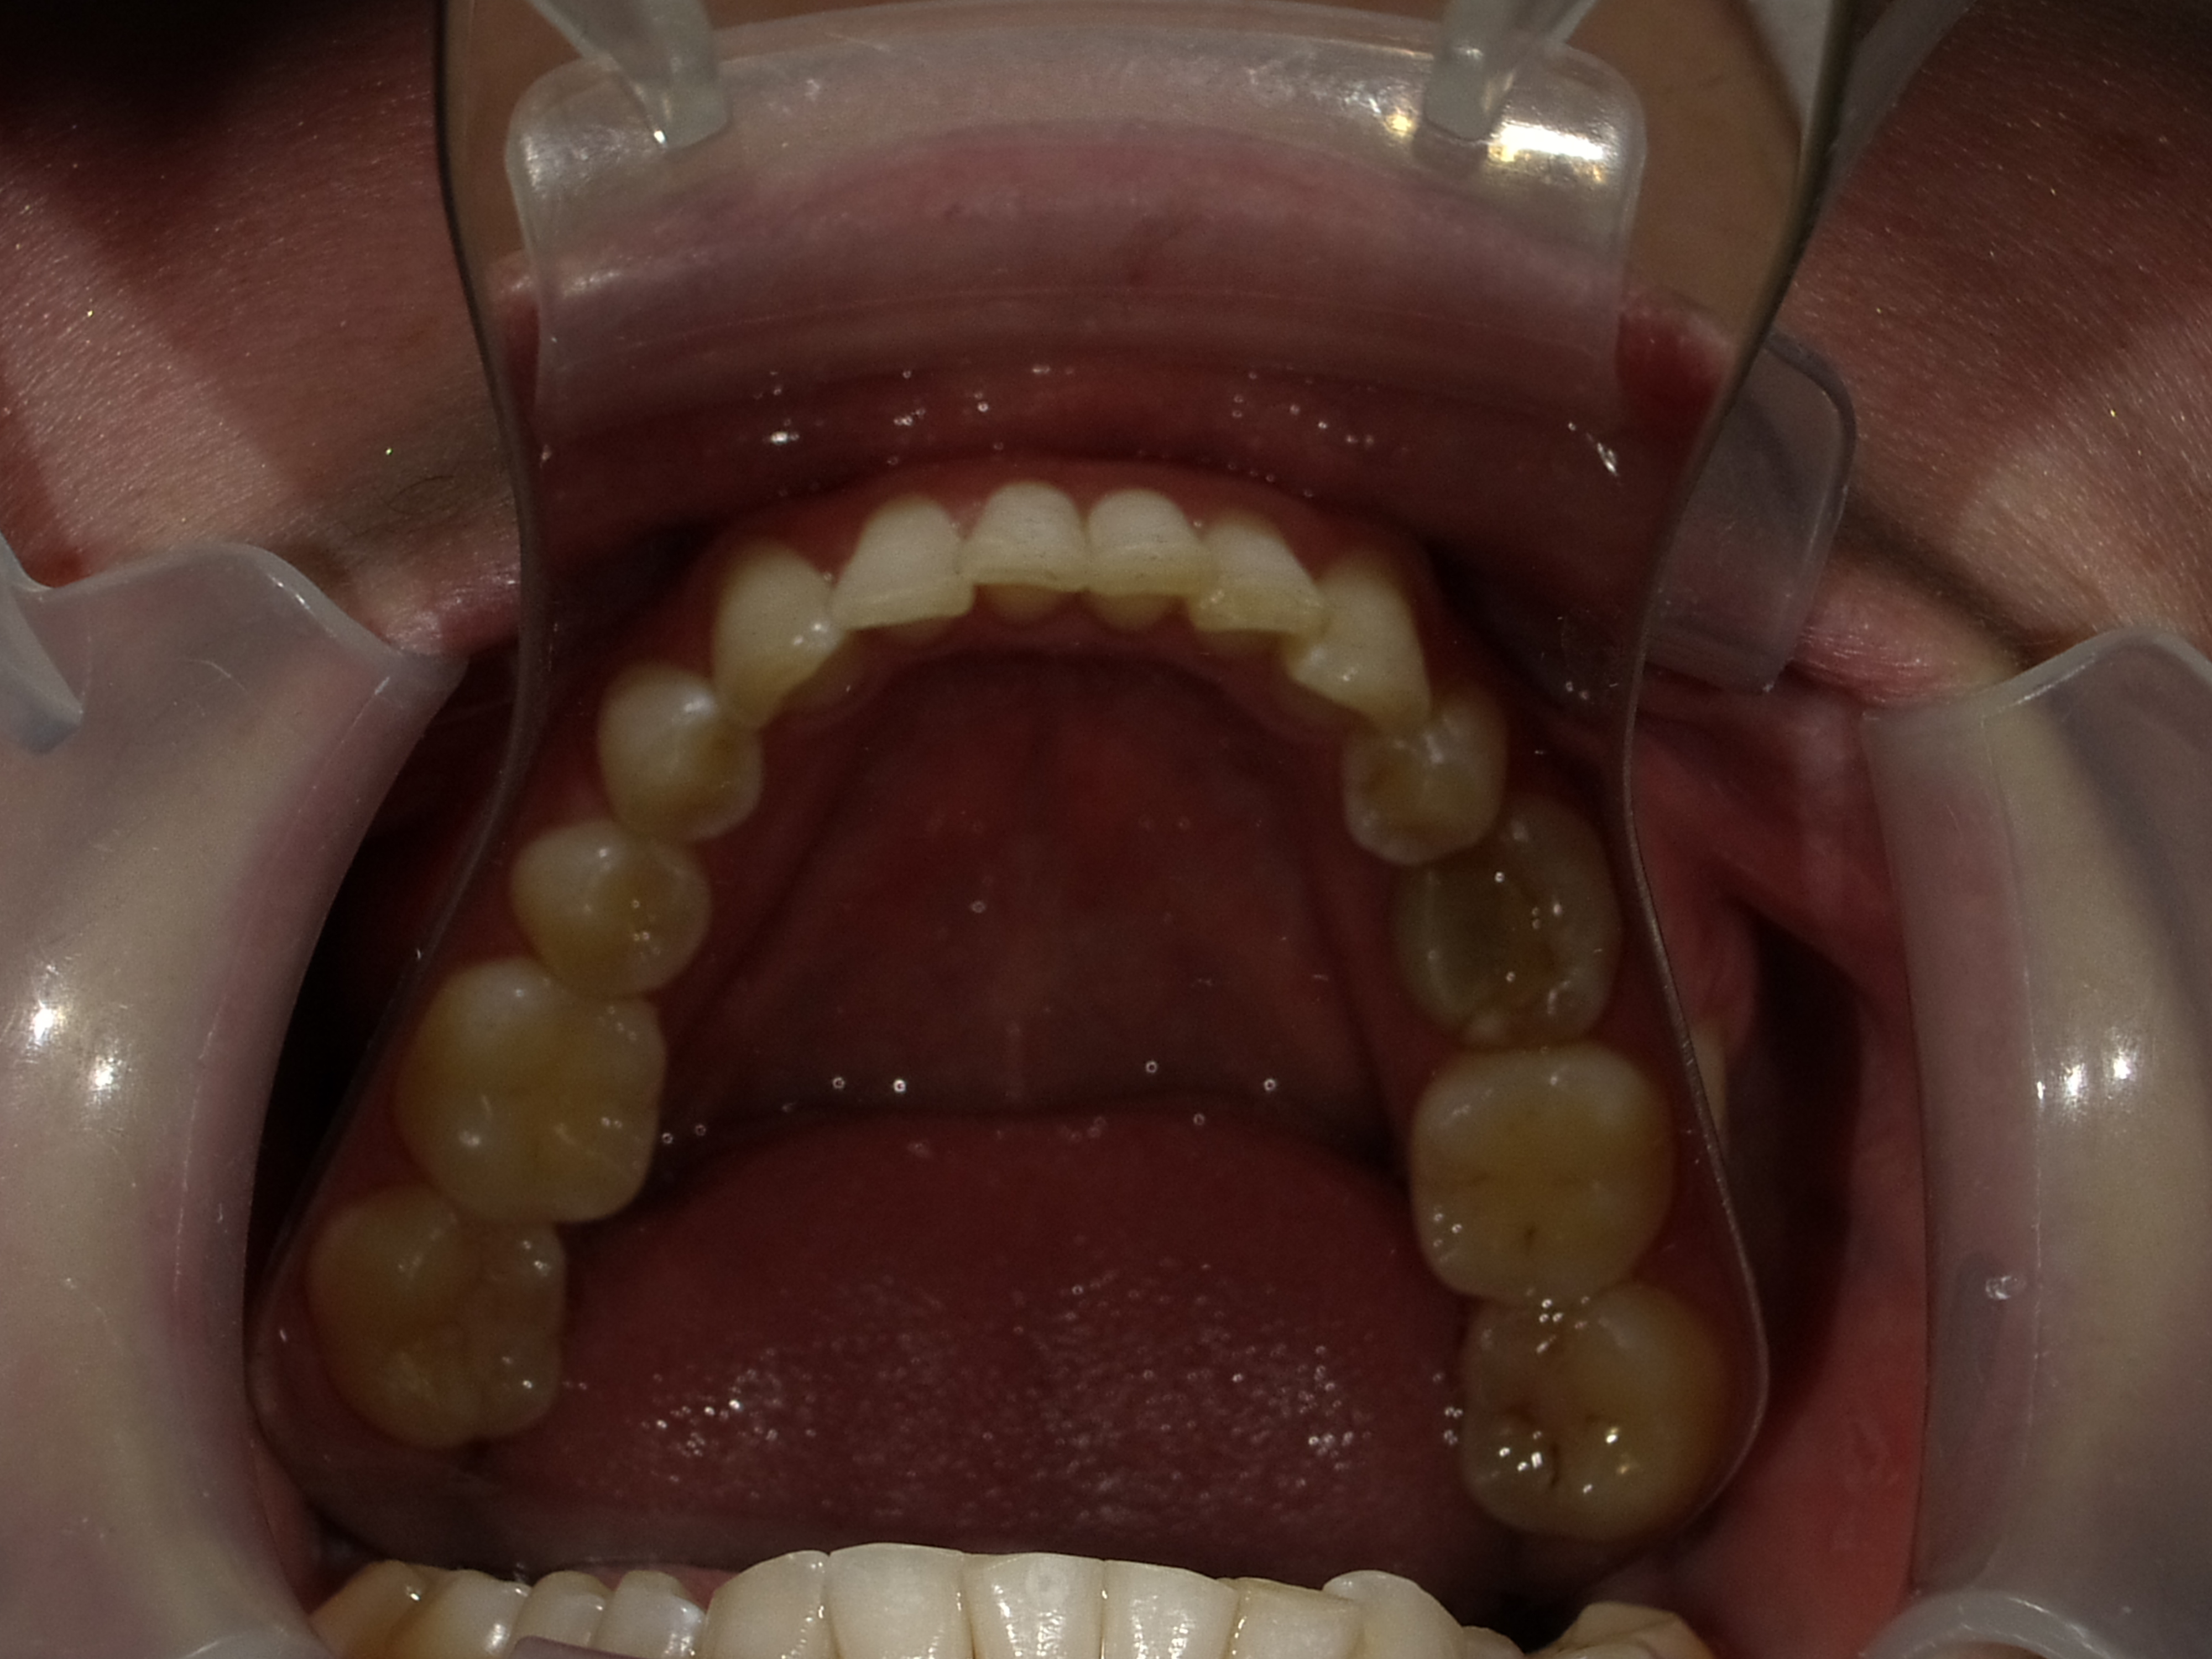

Patient Photographs

At a minimum, 4 photos are required.

1. Front view smile not retracted

2. Front view retracted

3. Maxilary retracted (with mirror is best.

4. Mandibular retracted.

Good lighting is key. A cell phone can be used with flash.